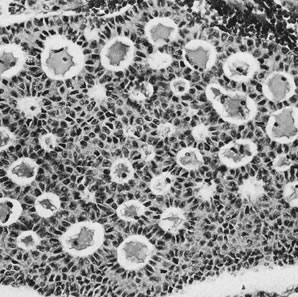

Thecomas are divided into two subtypes: the typical and the luteinized forms.17,18 Both tumors form solid masses composed of firm tissue that may be yellow throughout or white with focal areas of yellow coloration (Fig. 7). Microscopic examination of the typical thecoma shows the exclusive presence or marked predominance of pale, vacuolated, lipid-rich cells that resemble theca interna cells (Fig. 8). A fibromatous component may be present, and occasionally a minor number of granulosa cells are observed. The luteinized thecoma has a background of typical fibroma or thecoma but contains, in addition, large lutein cells (i.e., cells resembling those of the corpus luteum) (Fig. 9). The lutein cells may contain variable amounts of lipid in their cytoplasm.

Fig. 8. Thecoma (magnification, ×130).(Morris JM, Scully RE: Endocrine Pathology of the Ovary. St. Louis, CV Mosby, 1958.)